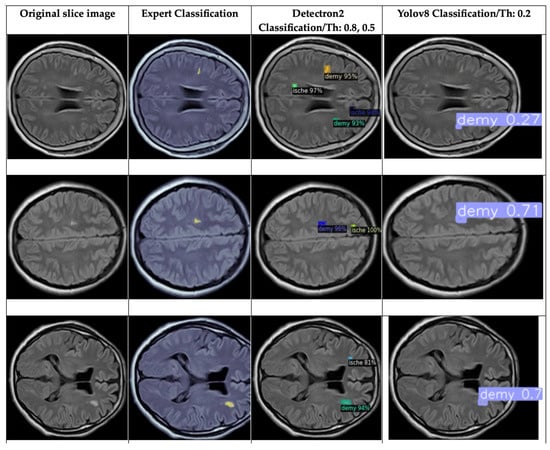

4.3. Detection and Classification

4.3.1. YOLOv8 Model for Detection and Classification

4.3.2. DETECTRON2 Model for Detection and Classification

4.5. Brief Comparison Results Between Expert Criteria and YOLO and Detectron2 Models for Classification of Ischemia and Demyelination Lesions